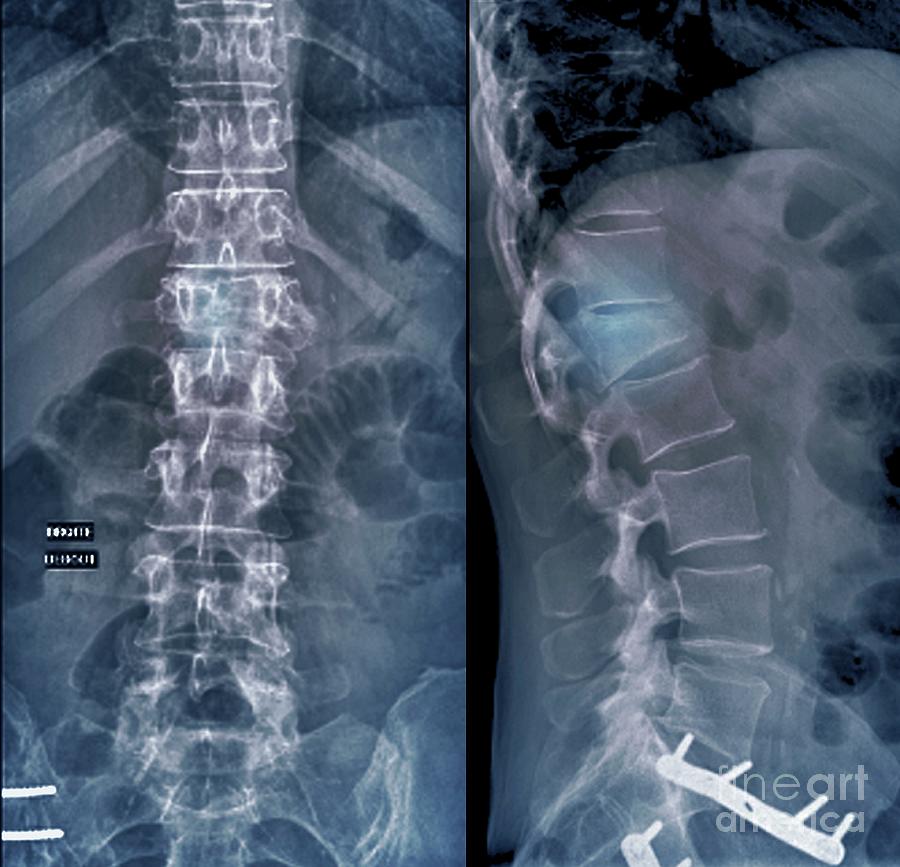

Plain X-ray of the thoracolumbar spine taken in anteroposterior view …

Scoliosis film x-ray lumbar spine AP : show spine bend in old aged …

Xray Image Of Adult Patient Spine Show Scoliosis Surgery Fix By Long …

Spondylosis And Scoliosis ( Film X-ray Lumbar – Sacrum Spine Show …

X-ray, anteroposterior view of the lumbosacral spine sh | Open-i

X-ray Of Lumbosacral Spine, Frontal Sagital View Scoliosis Royalty-Free …

Spondylosis and Scoliosis ( Film X-ray Lumbar – Sacrum Spine Show …

Xray Lumbar Spine Show Degenerative Change Of Disc And Body Of Spine …

X-ray image lumbar spine stock image. Image of disc, medical – 95002091

Spondylosis and Scoliosis ( film x-ray lumbar – sacrum spine show …

Spondylosis and Scoliosis ( Film X-ray Lumbar – Sacrum Spine Show …

Spondylosis ( film x-ray lumbo – sacral spine : show spondylosis at L2 …

X-ray image lumbar spine stock image. Image of column – 95002161